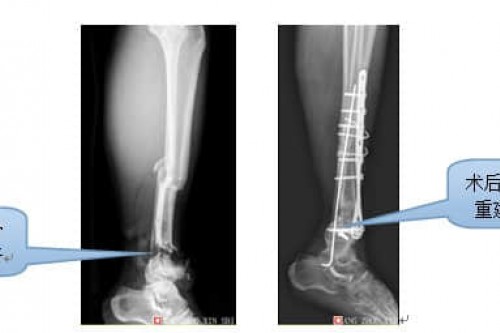

真实案例展示一: 舒先生,男,44岁,因车祸致左小腿中下段损伤入住骨科。术前检查见胫腓骨开放粉碎性骨折,皮肤和胫骨下段有缺损,碾压伤致组织挫伤严重,创腔内有泥沙、汽车油漆,污染严重。术中彻底清创,见胫骨下端关节面破碎成6小块,将各小块按解剖部